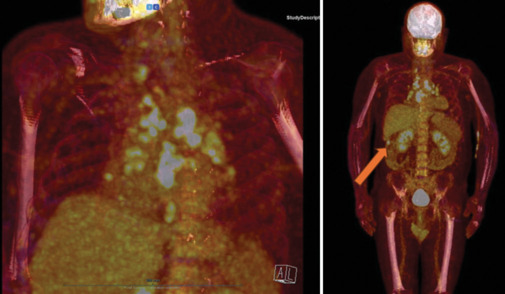

Cardiac sarcoidosis is an insidious condition with a highly variable clinical presentation that often mimics other diseases. Its diagnosis is particularly challenging, requiring a high index of suspicion and a comprehensive approach. Multimodality imaging plays a critical role in differentiating it from other conditions. We present a patient with cardiac sarcoidosis who also had concomitant coronary artery disease and colon cancer. The optimal therapeutic strategy for cardiac sarcoidosis remains uncertain. However, late gadolinium enhancement, a robust predictor of arrhythmic risk is crucial in guiding treatment decisions. This case report illustrates the risk of oversimplifying complex clinical scenarios by attributing signs and symptoms to a single disease, particularly in young, otherwise apparently healthy individuals. In such cases, clinicians must include rare diseases in their differential diagnosis.